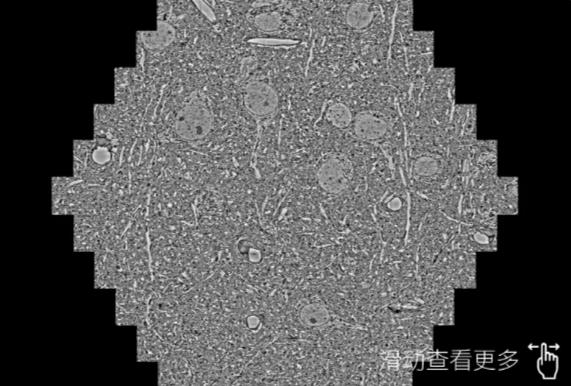

鼠脑切片。左图使用浙江蔡司浙江扫描电镜MultiSEM706对165μmx143pm面积区域成像,耗时仅需1.5秒。右图为鼠脑切片中30μm区域放大效果。样品由芝加哥大学B.Kasthuri提供。

使用蔡司高速浙江扫描电镜MultiSEM对1mm²人脑皮层组织进行高分辨成像,并对其中的各种细胞结构进行三维重构分析。左图展示了2x3mm²组织平面中锥体神经元的三维重构效果。右图显示了局部体积神经元三维重构。图像由哈佛大学chtman实验室提供,渲染图由D. Berger 制作。